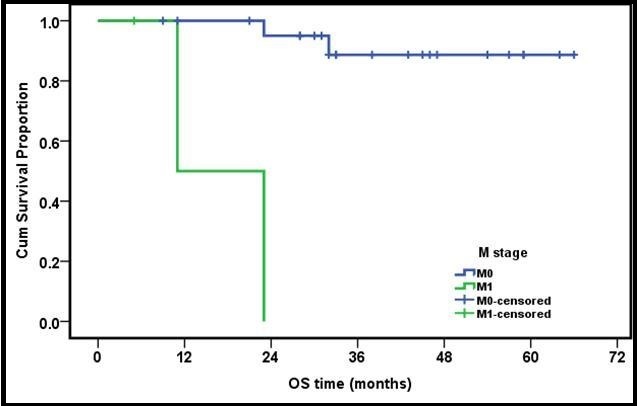

The OS for early stages (T1 and T2) was 100%, T3 (87%) while T4 cases were 72.7% with no statistical significance (p value =0.2). Similarly, OS for N0,1 was 88.8%, and for N2,3 82.3%, again with no statistical significance (p=0.39). On the other hand, OS for M0 was 91.3% and for M1 33.3% with statistical significance (p =0.032)( Figure 3 and Figure 4).

Figure 3.3 years OS of metastatic versus non metastatic group of patients

Twenty-three patients (88.4%) in the present series were stratified as M0, while 3 patients (11.6%) were M1. Their OS survival was 91.3% versus 33.3%. This was the only prognostic factor identified in our study.

In our study, the presence or absence of distant metastasis at presentation was found to be the only factor of statistical significance. Similar finding was reported by many other authors who reported age and sex having no prognostic significance20, 21, 24. Good responders to neo-adjuvant chemotherapy were found to have a better OS and EFS in some studies 20, 22, 25, 30, while others -including the present study showed no statistical difference according to initial response 21, 24, 26, 27.